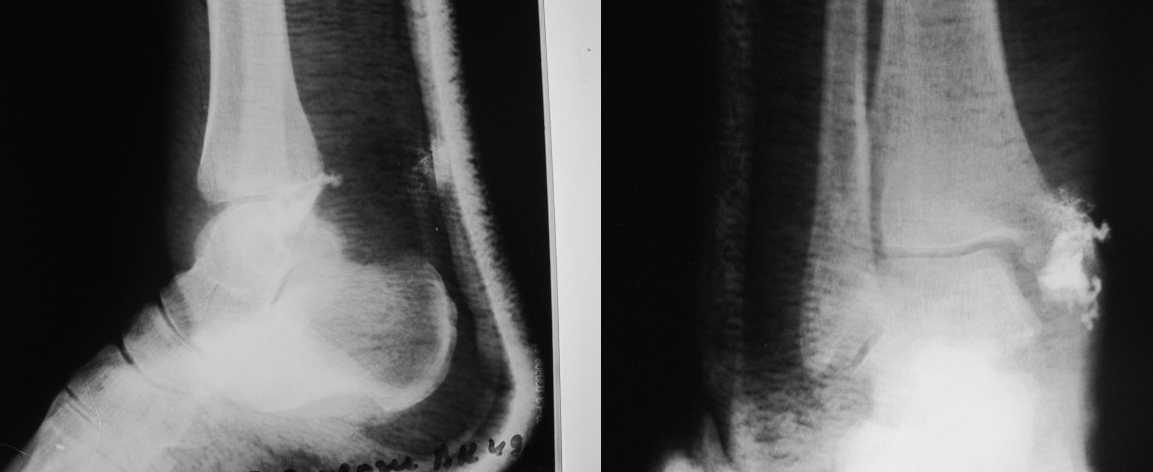

Уважаемые коллеги! Прошу прощения за собственную невнимательность. У больной травма не 1 января 2011г., а 1 декабря 2010г., т.е. уже 2 месяца.

Прилагаю данные фистулогрфии. Основной вопрос, все же, лечить консервативно или оперативно? Если оперативно, то какой объем? А что если прийдеться резецировать всю медиальную лодыжку!?